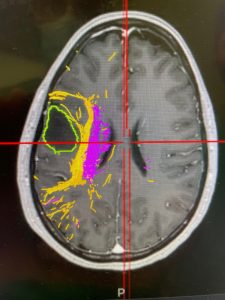

Αριστερά: Μαγνητική δεσμιδογραφία με την οποία απεικονίζεται η σχέση του όγκου με τα κρίσιμα δεμάτια του εγκεφάλου (επί τω προκειμένω: SLF και πυραμιδική οδός). Δεξιά: Εικόνα από το χειρουργείο (προσωπικό αρχείο νευροχειρουργού Παντελή Σταυρινού)